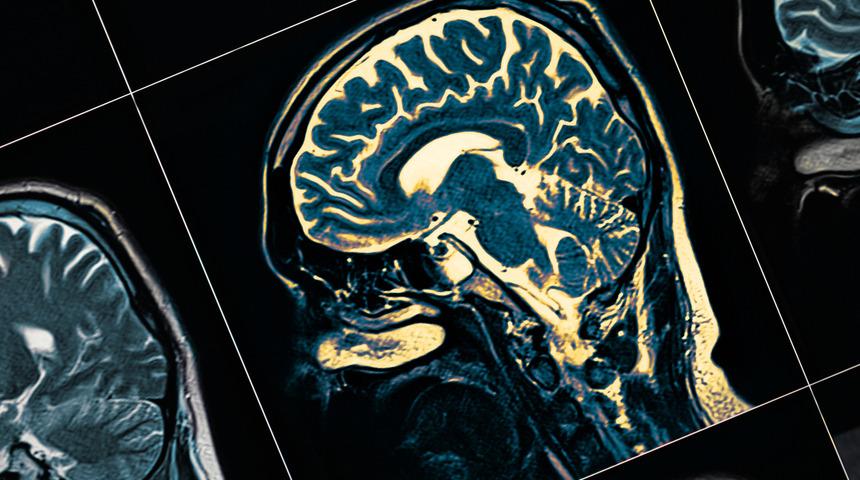

Beyin ölümü, beyin sapı denilen özel beyin bölgesinin fonksiyonlarının geri dönüşü olmaksızın yok olmasına denir. Organ bağışı konusunda kritik bir öneme sahip olan beyin ölümü tıbbi olarak ölüm sayılır. Beyin ölümü nasıl gerçekleşir, merak ediyorsanız tüm detayları yazımızda bulabilirsiniz.

İnsan vücudunun kafatası içerisinde bulunan tüm beyin, beyincik ve merkezlerin yer aldığı beyin sapının fonksiyonlarının geri dönüşü olmaksızın yok olmasına beyin ölümü denir. Beyin ölümü tıbbi olarak ölümü ifade eder. Bununla birlikte kalp, böbrekler, solunum organlarının belli bir zaman sonra işlevinde azalma görülür. İleri yaşam desteği ile bir süre bu organların hayatta kalması sağlanır; ancak desteğin kesilmesi ile birlikte tüm organ fonksiyonları kaybedilir. Mutlak ölüm ile sonuçlanan bu sürecin özellikle organ nakli söz konusu ile doğru, eksiksiz ve zamanında yapılması çok önemlidir. Burada en büyük sorumluluk doktorlara düşmektedir.